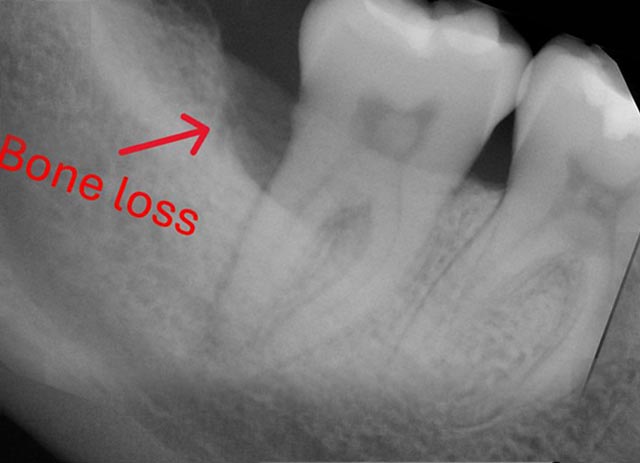

Implant Bone Grafting - Before And After

Tooth Bone Grafting - Before And After